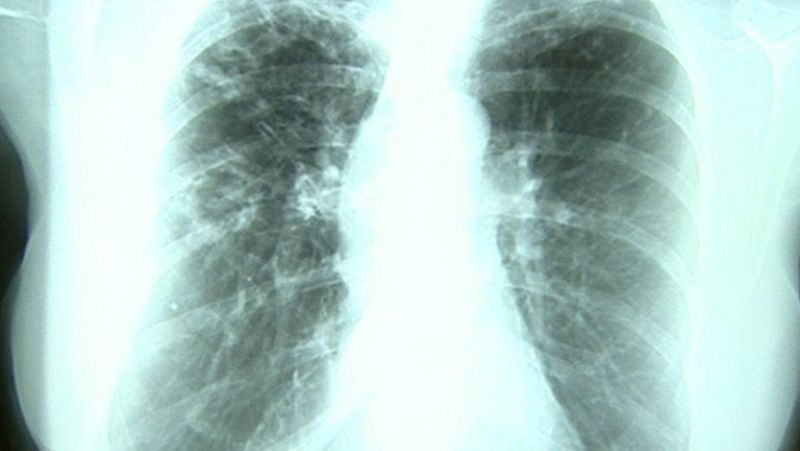

Un paciente que padece tuberculosis sopla aire como parte del tratamiento médico

Un paciente que padece tuberculosis sopla aire como parte del tratamiento médico EFE/EPA/BILAWAL ARBAB